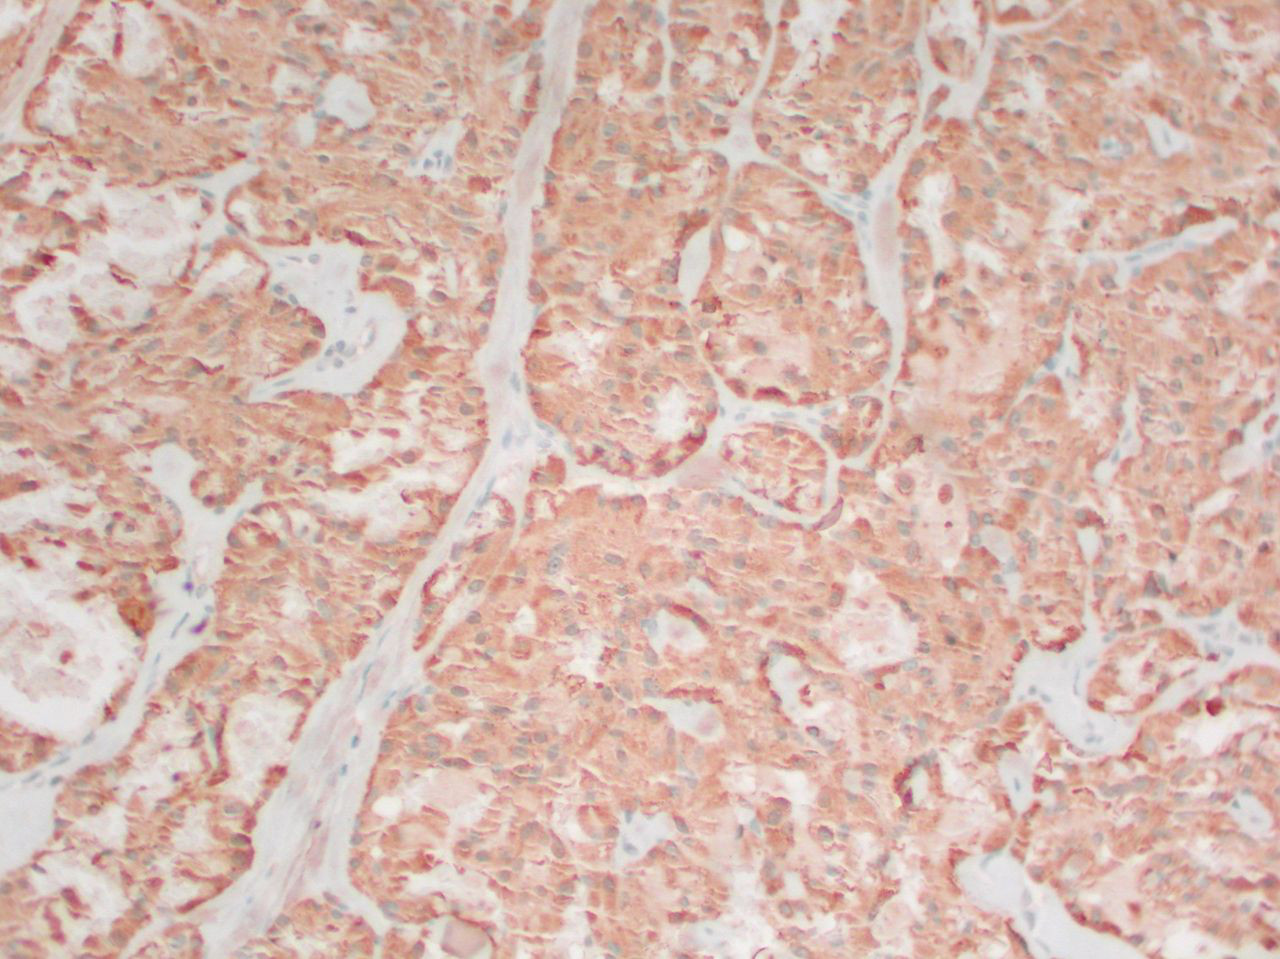

Medullary thyroid cancer: calcitonin stain

Mohan V et al. BMJ Case Reports CP 2019;12:e230446; used with permission

See this image in context in the following section/s: